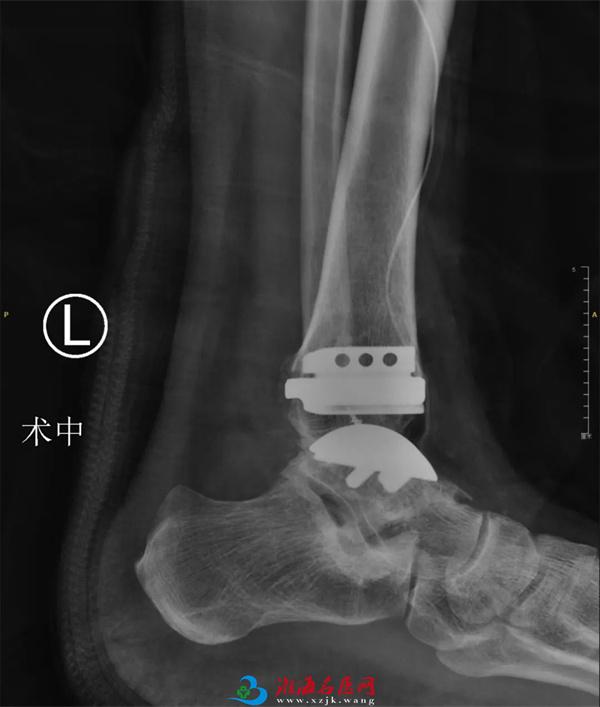

经过周密的术前准备,1月18日,石荣剑主任医师、曹广超副主任医师和李亮主治医师手术团队为患者进行了左踝人工全踝关节置换手术,手术顺利。术中见关节歪向内侧,骨赘增生严重,首先松解挛缩的韧带,使用提前精准设计打印的3D导板,透视调整力线,截骨安装适合型号的关节假体,最后调整内外侧软组织平衡,增加关节稳定性。

等待装假体(左图)安装假体后(右图))

正侧位术后X光片(同时修复加固损伤的外侧副韧带)